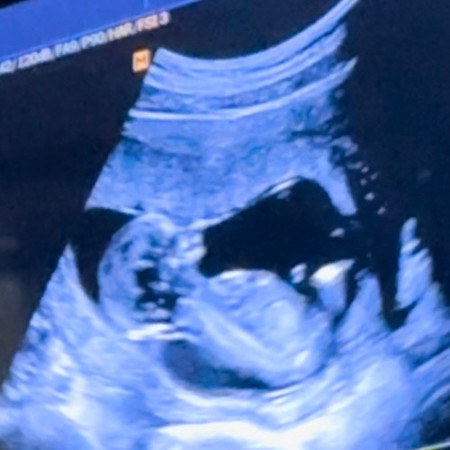

อัลตร้าซาวน์ดูชั้นคอหนา

สอบถามแม่ๆหน่อยค่ะ แบบนี้เรียกชั้นคอหนามั้ยค่ะ ซาวตอน 13 weeks พึ่งมาสังเกตค่ะ หรือแบบนี้ปกติค่ะ

นี่มองว่าเป็นไหล่น้องนะคะแม่ มาบังช่วงคอพอดี

ถ้าหมอไม่ได้บอกอะไรเพิ่มก็คือปกติค่ะ